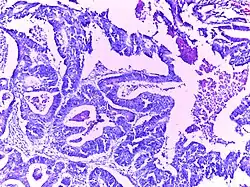

Adenocarcinoma colon | Micrograph of carcinoma colon showing malignant glands.Nuclei are small and vesicular, located at the bottom of the cell. The cells show increased nucleocytoplasmic ratio. | Category: Histopathology of colorectal adenocarcinoma | Colorectal carcinoma |

![]() |